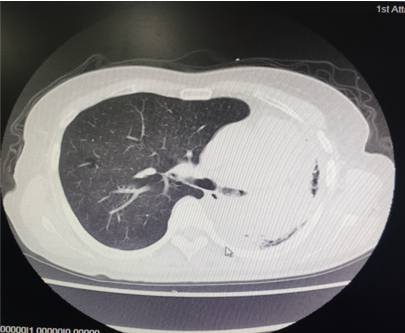

为提升肺癌前线免疫联合抗血管治疗的诊疗观念,学习与追踪肺癌领域诊疗最前沿知识,充分交流免疫/抗血管用药不良反应管理临床经验,【An例说】肺癌病例项目,征集大量临床高质量免疫联合抗血管治疗肺癌病例,并邀请全国各区域中青年及高职称医生与顶级TOP KOL互动发声!通过理念结合实践,研究结合病例,线上联动,共同促进学术由KOL/ROL向中青年医生下沉,为提升我国肺癌诊疗整体水平势在必行。免疫治疗的出现,特别是以PD-1/PD-L1为代表的免疫检查点治疗的出现,对于转移性的晚期肺癌患者而言,给患者增加了更多治疗的选择,同时,多项临床研究表明免疫治疗显著延长了患者的生存期及生活质量。为此,河北北方学院附属第一医院为您带来一例“双安疗法”用于二线治疗小细胞肺癌病例的治疗分享。 案例详情 基本情况 患者,霍xx,女,60岁。 初治时间:2020-10-16 既往史:COPD 4年,间断口服茶碱治疗,否认其他慢性病史及传染病史。否认过敏史。 个人史:无特殊 家族史:无特殊 ADL评分:90分;Khorana评分1分 入院初步检查结果 体格检查: COPD 4年,间断口服茶碱治疗,否认其他慢性病史及传染病史。否认过敏史。 个人史、婚育史、家族史无特殊。 辅助检查 血常规、肝肾功、凝血功能无明显异常。 肿瘤标志物(特异性+异常指标)。 肿瘤标志物变化趋势 NSE(神经元特异性烯醇化酶)变化趋势: NSE变化趋势 基线情况: 2020-10-16,患者无明显诱因出现咳嗽、咳痰,偶有痰中带血,伴胸闷气短4个月于我院就诊:查胸部CT:胸廓左侧塌陷,左肺上叶尖后段及下叶支气管截断,左肺下叶见软组织密度团块。右肺中叶容积小。左主支气管内见高密度影,纵隔多发肿大的淋巴结,胸膜厚,左侧少量胸膜腔积液。 浅表淋巴超声、全身骨扫描等检查提示肺外脏器未见异常。 肺部CT提示左肺占位伴阻塞性肺炎、纵隔淋巴结肿大,左侧胸腔积液。 患者遂就诊于解放军81集团军医院行支气管镜检查提示小细胞肺癌。 影像学检查 诊断结果 1.左肺小细胞肺癌(广泛期)伴胸膜转移、伴纵隔淋巴结转移 2.阻塞性肺炎 3.慢性阻塞性肺疾病 诊疗依据 (CSCO)小细胞肺癌诊疗指南2020 05治疗经过 第一阶段治疗: 胸部CT对比:较前片(2020-10-16)对比:左肺上叶复张且高密度影明显吸收;左肺占位及纵隔淋巴变化不明显,左侧胸腔积液基本吸收。 胸部CT检查对比 胸部CT对比:较前片(2020-11-26)对比:左肺占位变化不明显;纵隔部分淋巴结增大。 胸部CT检查对比 胸部CT对比:较前片(2020-12-30)对比,左肺占位明显增大,隔巴结增大,左侧胸腔新发积液,左肺上叶膨胀不全,左肺上叶新发片状高密度影。 胸部CT检查对比 胸部CT对比:较前片(2021-03-02),左肺占位性病变较前增大,纵膈肿木淋巴结较前增大。 胸部CT检查对比 胸部CT对比:较前片(2021-04-04)左肺中心型肺Ca伴左肺不张,较前增大。右肺中叶不张。纵隔多发肿大融合淋巴结,部分包绕上腔静脉,较前增大。心包少量积液、主肺动脉干增粗。左侧胸腔积液(±)。 胸部CT检查对比 头颅CT对比:2021-06-21头颅CT:考虑左枕叶、右颞叶转移瘤。尾状叶头密度增高。 头颅CT检查对比 腹部CT:较前片(2021-04-04)左肾上腺增粗,考虑转移瘤? 腹部CT检查对比 第二阶段治疗:免疫+安罗替尼。ADL评分:70分;Khorana评分3分。 胸部CT对比:对比前片(2021-06-21),左肺占位减小,纵隔部分淋巴结减小,胸腔积液吸收。 胸部CT检查对比 头颅CT对比:对比前片(2021-06-21):颅内占位变化不著。 头颅CT检查对比 胸部CT对比:对比前片(2021-07-27):左肺占位减小,纵隔部分淋巴结减小;左肺上叶片状高密度影略显吸收。 胸部CT检查对比 胸部CT对比:对比前片(2021-8-23):左肺占位及纵隔淋巴结有所减小。 胸部CT检查对比 胸部CT对比:对比前片(2021-10-29):左肺占位及纵隔淋巴结变化不著。 胸部CT检查对比 头颅CT对比:较前片(2021-07-01)对比:左枕叶、右颞叶占位明显减小。 头颅CT检查对比 胸部CT对比:对比前片(2021-11-30):左肺占位及纵隔淋巴结变化不著,腹部较前变化不著。 胸部CT检查对比 目前情况:患者神清,精神尚可,无咳嗽咳痰,偶有喘憋气短,饮食睡眠尚可,二便正常。 面部及双手皮疹样改变。 目前诊断: 1. 左肺小细胞肺癌(广泛期)伴胸膜转移、伴纵隔淋巴结转移、伴脑转移、伴肾上腺转移 2. 慢性阻塞性肺疾病 3. 下肢静脉血栓形成 4. 低钠血症 ADL评分:80分;Khorana评分2分 06病程回顾 专家点评 该病例,女性,无吸烟史,既往自2014年开始反复因咳嗽、咳痰、咯血于我院门诊或住院治疗,诊断为右中叶、双下肺基底段支气管扩张伴感染。2020年10月再次因咳嗽、咳痰、咯血行肺CT检查,检查结果示:支气管扩张、左下肺占位。后经支气管镜检查左下肺癌,病理为小细胞癌。结合肺CT:纵隔淋巴结肿大,左侧胸腔积液;临床诊断为:原发性支气管肺癌(左下广泛期小细胞肺癌)。PS评分1分,依据2020年CSCO小细胞肺癌指南Ⅰ级推荐选择化疗+免疫治疗,化疗方案:CE/EP,IC/IP,免疫治疗:atezolizumab。本病例中,患者因经济条件所限,未使用atezolizumab,化疗采用CE\EP\ZP一线及二线LE(共计7疗程),肺部病灶增大,左肺完全不张,脑转移,肾上腺转移,PS评分3分。再次依据CSCO指南,行颅脑放疗,采用PD-1(卡瑞丽珠单抗)+EP+安罗替尼(口服小分子多靶点抗血管生成药物)2个疗程后,肺部病灶明显缩小,颅内病灶消失,评效为PR;后因卡瑞丽珠单抗副作用:反应性皮肤毛细血管增生症(RCCEP)及手部皮肤皲裂,改换为派安普利单抗+EP+安罗替尼治疗,直至目前。左肺完全复张,病情明显改善,PS评分降至2分。 该患者全程治疗过程分析,单纯化疗疗效不显著,PD-1联合抗血管生成靶向药物后,使得患者病情控制,生存带来了希望。“双安”治疗方案副作用小,对PS评分高的患者也适用。派安普利单抗是唯一采用IgG1亚型且经FC段改造的新型PD-1单抗,副作用较国产其他IgG4亚型 PD-I更小;安罗替尼为口服小分子多靶点络氨酸酶抑制剂,靶点更加全面,疗效更优。采用“双安”治疗广泛期小细胞肺癌,本例虽为个例,但为临床医生提供了可践行的治疗方向,也期待着更多临床研究数据的公布,为小细胞肺癌的治疗提供强有力的治疗依据。 病例分享 王布 教授 河北北方学院附属第一医院呼吸科副主任医师,医学硕士 河北省中西医结合睡眠专业会委员 张家口市抗癌协会肺癌专业委员会委员 世界中医药学会联合会整合肿瘤专业委员会委员 在《Translational Cancer Research》、《Journal of biological regulators &homeostaticagents》、《中国临床药理学》、《中华结核与呼吸杂志》等杂志上发表学术论文10余篇,其中《川芎嗪联合顺铂影响Lewis肺癌小鼠移植瘤生长及微血管生成的研究》论文在2015年中国药学大会暨第十五届中国药师周上报告交流 荣获河北省科技进步三等奖1项,河北省医学会科技奖一等奖1项 目前以第一主研人主持河北省科技厅课题1项,市厅级课题2项 以第二主研人主持张家口市财政厅支持课题1项;河北省政府资助专科能力建设和专科带头人培养课题1项 获“河北省抗击新冠肺炎先进个人”、“河北省优秀共产党员”、“河北省冀青之星”、张家口市“最美科技工作者”,“张家口市抗击新冠肺炎先进个人”、“张家口市优秀共产党员”等荣誉称号。 专家点评 支学军 教授 河北北方附属第一医院主任医师 教授,河北北方学院硕士研究生导师 任河北省医学会内科学分会委员 张家口市医学会呼吸分会常务委员兼秘书 张家口市抗癌协会理事会理事 张家口市抗癌协会肿瘤临床化疗专业委员会常务委员 张家口市抗癌协会抗癌药物专业委员会常务委员等职务 从事呼吸科工作30余年,擅长肺部感染性疾病、肺癌、肺结核等疾病的诊治。